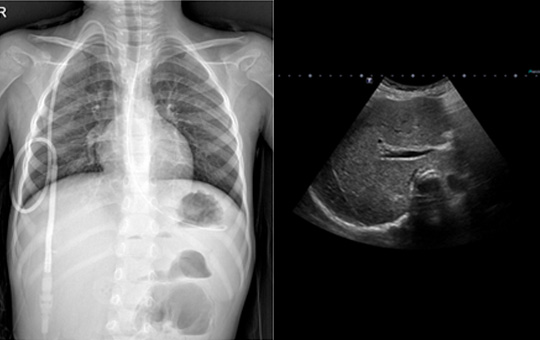

전체적인 케이스는 증가하였으나 임상적으로 2008년이후 감소추세임